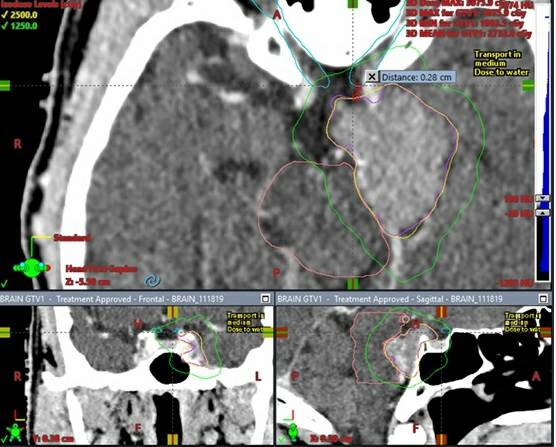

What is the long term control Sporadic Vestibular Schwannoma after radiosurgery?

LC 5, 10, & 15 years 96%, 92%, & 91%

13% pseudoprogression median time 0.5 yrs (only 4% >5yr after SRS) doi.org/10.3171/2025.8…